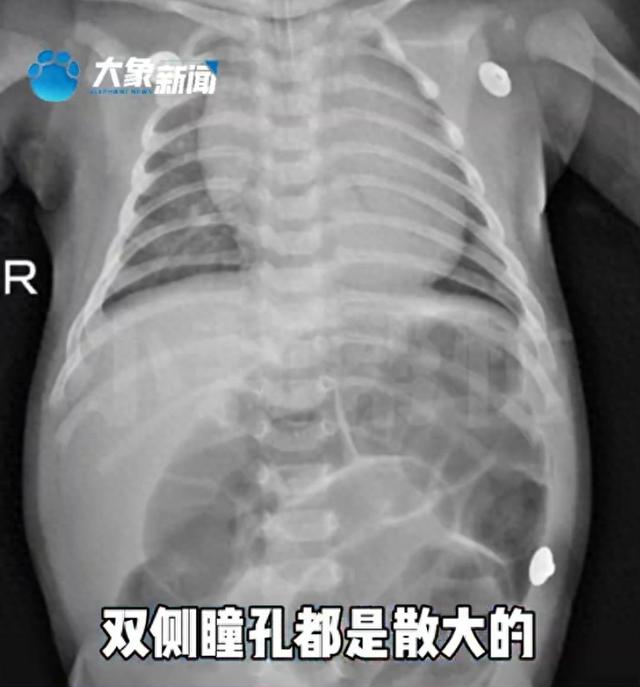

医生迅速为小林林进行气管插管和机械通气,解决了呼吸问题。然而,孩子的腹胀症状仍未缓解,且瞳孔对光反射消失,病情复杂。

会诊后专家一致怀疑小林林为肉毒杆菌食物中毒,仅52天的宝宝为何会肉毒杆菌中毒?